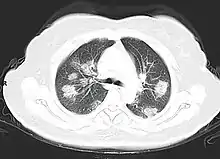

Imaging

Chest CT scans may be helpful to diagnose COVID‑19 in individuals with a high clinical suspicion of infection but are not recommended for routine screening.[174][186] Bilateral multilobar ground-glass opacities with a peripheral, asymmetric, and posterior distribution are common in early infection.[174][187] Subpleural dominance, crazy paving (lobular septal thickening with variable alveolar filling), and consolidation may appear as the disease progresses.[174][188] Characteristic imaging features on chest radiographs and computed tomography (CT) of people who are symptomatic include asymmetric peripheral ground-glass opacities without pleural effusions.[189]

Many groups have created COVID‑19 datasets that include imagery such as the Italian Radiological Society which has compiled an international online database of imaging findings for confirmed cases.[190] Due to overlap with other infections such as adenovirus, imaging without confirmation by rRT-PCR is of limited specificity in identifying COVID‑19.[189] A large study in China compared chest CT results to PCR and demonstrated that though imaging is less specific for the infection, it is faster and more sensitive.[173]